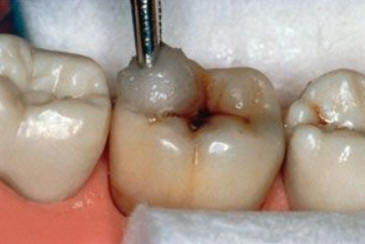

Una morfología de la fisura estrecha, con forma de botella de "Coca-Cola" genera un nicho ecológico ideal para la colonización de cualquier bacteria productora de ácidos. Al no poder remover en forma períodica dicho biofilm de una zona tan estrecha, el ataque ácido genera una lesión cariosa en la dentina, con un aspecto de esmalte intacto a la inspección visual, o sea un típico código 3 y 4 de ICDAS Completo. (Caries Moderada para el ICDAS COMBINADO)

Por este motivo es importante realizar el sellado de las fosas y fisuras de molares y premolares cuando comienza su erupción dentaria, como método de prevención eficaz de caries.

Código 3 (Caries moderada) in vitro. Los códigos 3 in vivo debe ser sellado para evitar el avance del proceso carioso. (MNO)

Código 4 (Caries moderada) in vitro. Los códigos 4 in vivo deben ser tratados en forma operatoria con preservación dental (MOPD), porque presentan dentina infectada.